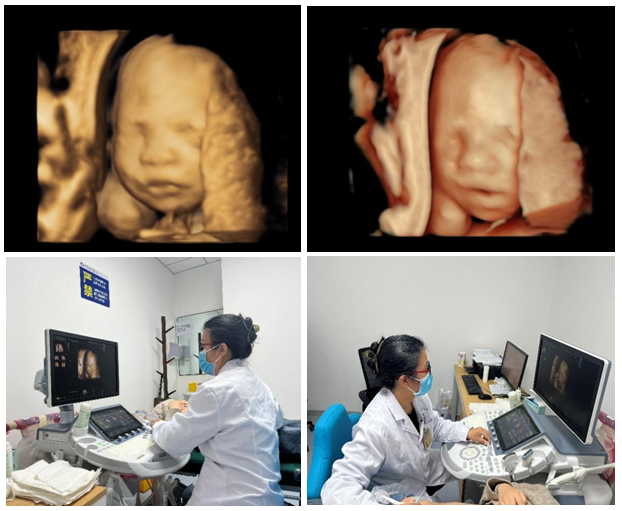

10月30日,三级片 超声诊断中心西咸院区开展第一例胎儿心脏彩色多普勒超声检查,同时开展了超声诊断中心西咸院区第二例输卵管超声造影。

10月31日,超声诊断中心西咸院区为一位29岁的二胎孕妇,成功开展胎儿四维系统彩色多普勒超声检查,这是西咸院区的第一例胎儿四维系统超声检查。